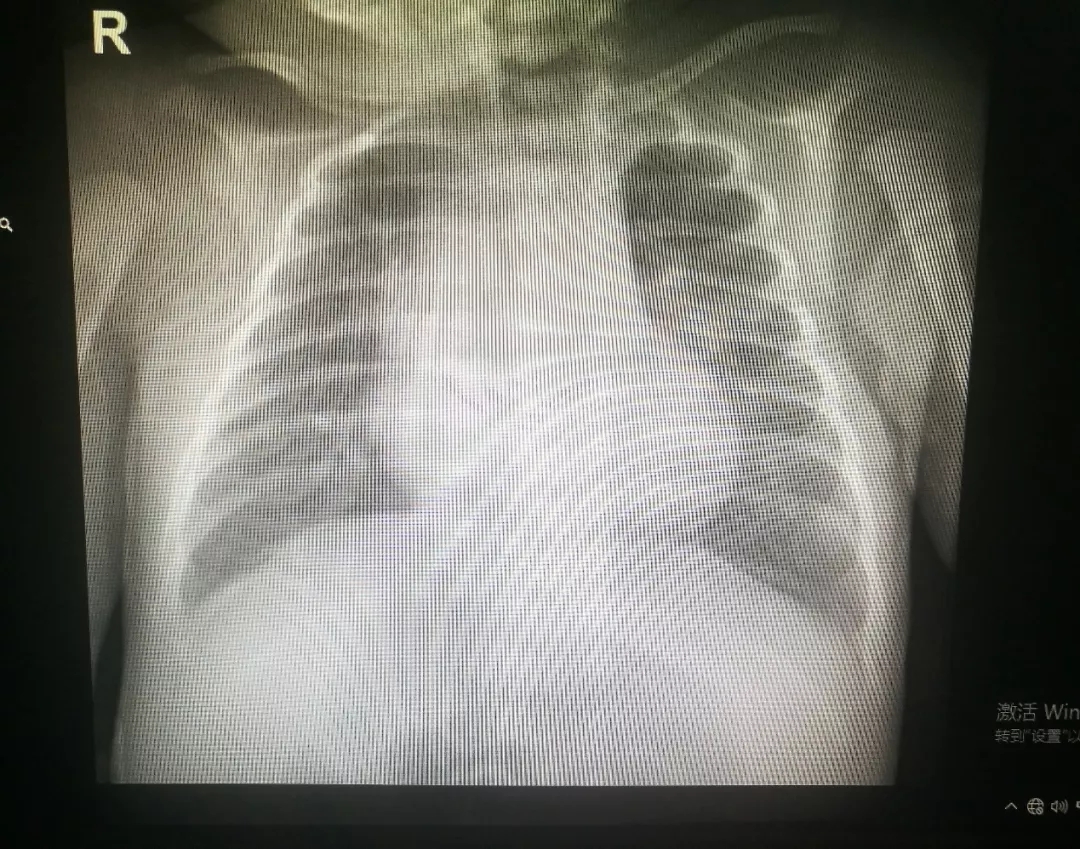

术后胸片

在儿内科副主任韦瑞含娴熟的操作下,支气管镜顺利进入患儿右主支气管腔及各肺段支气管,镜下可见大量白色粘液痰栓,考虑这些粘液痰栓可能是导致右肺不张的罪魁祸首,必须想办法清理,经过反复吸引并予药物反复行支气管肺泡灌洗后,气管内痰液明显减少。

操作过程顺利,患儿生命征稳定,操作结束后患儿无气促、紫绀、呼吸困难症状,经皮血氧饱和度维持在正常水平,复查血气分析各项指标正常。术后韦瑞含副主任说道:“由于新生儿气道很小,再加上早产儿本身生命脆弱,缺氧耐受能力差,手术操作难度增大,对于医生无疑是个很大的挑战。”

在新生儿科医护团队的悉心治疗及护理下,患儿病情稳定,逐渐予撤除有创呼吸机改为经鼻高流量给氧支持治疗,复查胸片提示右肺不张明显好转,治疗效果显著。现患儿处于康复阶段。该患儿成功实行电子支气管镜灌洗治疗,标志着我院新生儿支气管镜诊疗技术又上了一个新的台阶。